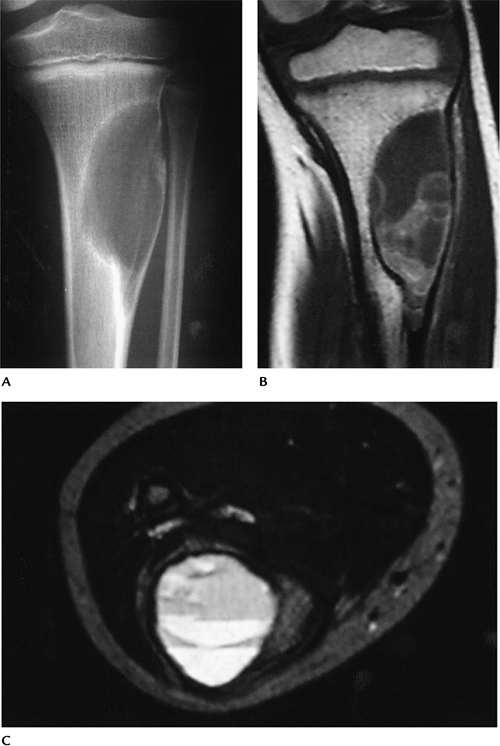

![]() |

|

FIGURE 10-35 Adamantinoma in a 21-year-old man. (A) Radiograph showing a lytic expanding lesion with cortical involvement in the midtibia. Sagittal T1-weighted (B) and axial T2-weighted (C) images showing a muscle intensity lesion on T1-weighted (B) and high-intensity lesion on T2-weighted (C) MR images.